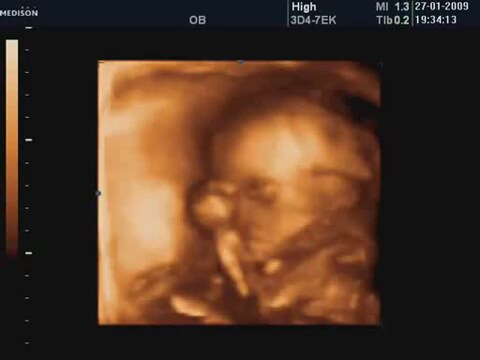

23 Haftalık Bebeğin 4 Boyutlu Ultrason Görüntüsü